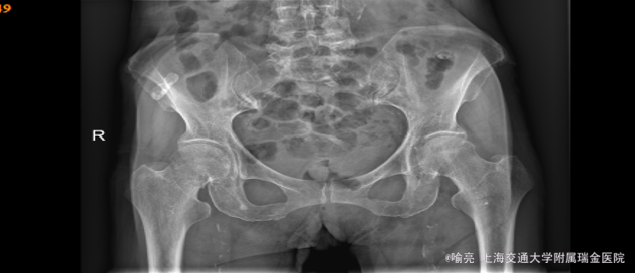

主诉:外伤后右侧髋部疼痛1天。 病史:患者昨日行走时被人撞倒致右髋部摔伤,当即感右髋部疼痛难忍,伴活动受限,无感觉障碍,皮温正常,遂来我院急诊就诊,行骨盆正位片示右侧股骨颈骨折。,急诊拟“右股骨颈骨折”收治入院。患者自发病以来,神清,精神可,胃纳、睡眠可,二便无殊,体重无明显变化。

查体:右髋部叩痛(+),右下肢外旋畸形,未见肿胀,血运、感觉未见明显异常,左膝关节、踝关节、足趾活动可,血运正常 辅助: x片示右侧股骨颈骨折

诊断:右侧股骨颈骨折 治疗:右侧股骨颈骨折闭合复位内固定术